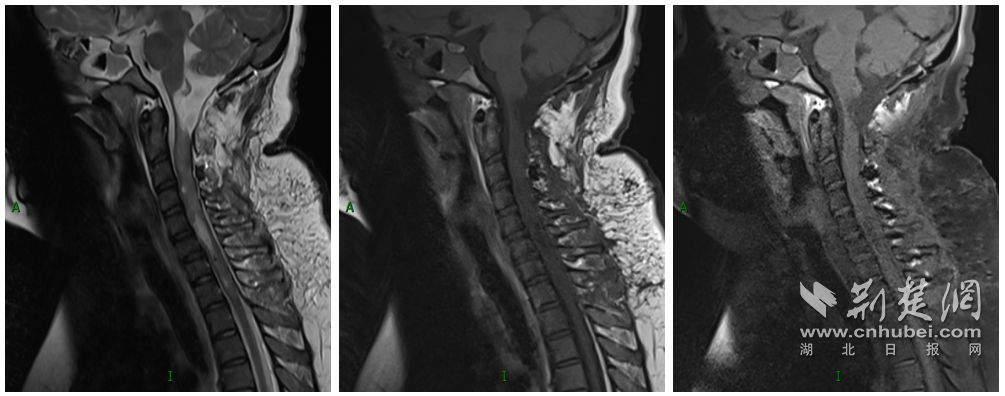

图为:完整切除4个孤立病灶:(从左往右)延髓-C2、C4、C5-7及T1椎体水平病灶

11月26日,在麻醉科、手术室、神经重症等多学科的配合下,周迎春教授、朱文德副教授带领团队为小婷实施这台高难度手术。术中,在神经电生理监测下,专家们借助显微镜高倍放大术野,沉稳操作,耐心细致地分离肿瘤与周围血管及神经的粘连,经过近5小时显微操作,最终完整切除病变组织。得益于术者丰富的手术经验和默契的团队配合,小婷平稳地度过了手术难关,脑干和脊髓功能得到了最大限度的保留,术后并未出现呼吸肌麻痹和肢体瘫痪。术后病理结果提示,病灶为室管膜瘤(WHO2级),这是一种低度恶性肿瘤。

图为:术后MRI显示病灶完整切除,正常延髓受压菲薄